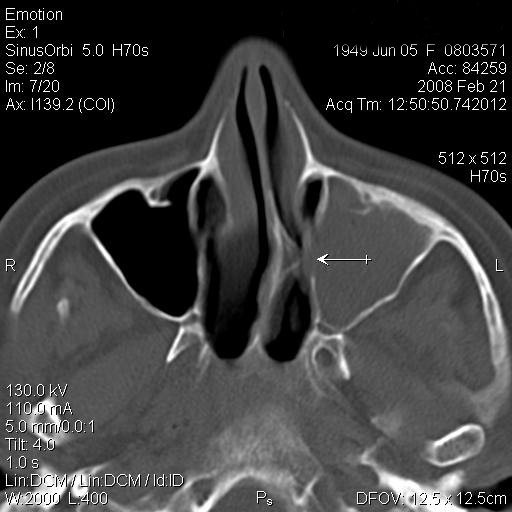

JFC Sinusitis maxilar. Espolón septal.